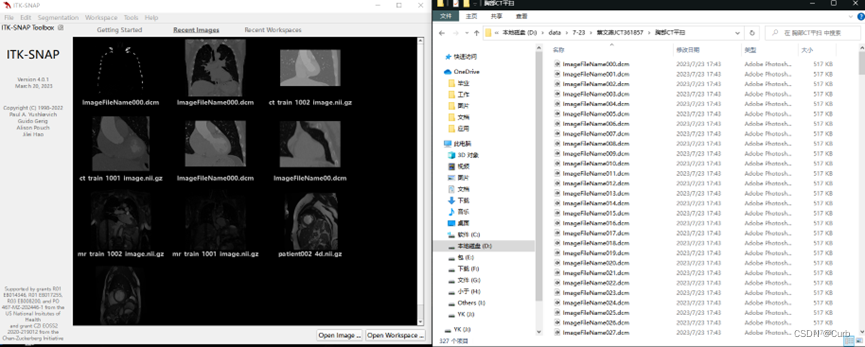

1 初始界面

2 导入病例文件

方法一:

再点击“open main image”

打开相应文件路径下的 .dcm 文件即可(一个病例对应多个dcm文件,打开任意一个就会对应打开这个病例的所有dcm)

方法二:

采用直接拖动的方式

将右边文件夹中其中一个.dcm文件拖拽到ITK-SNAP中